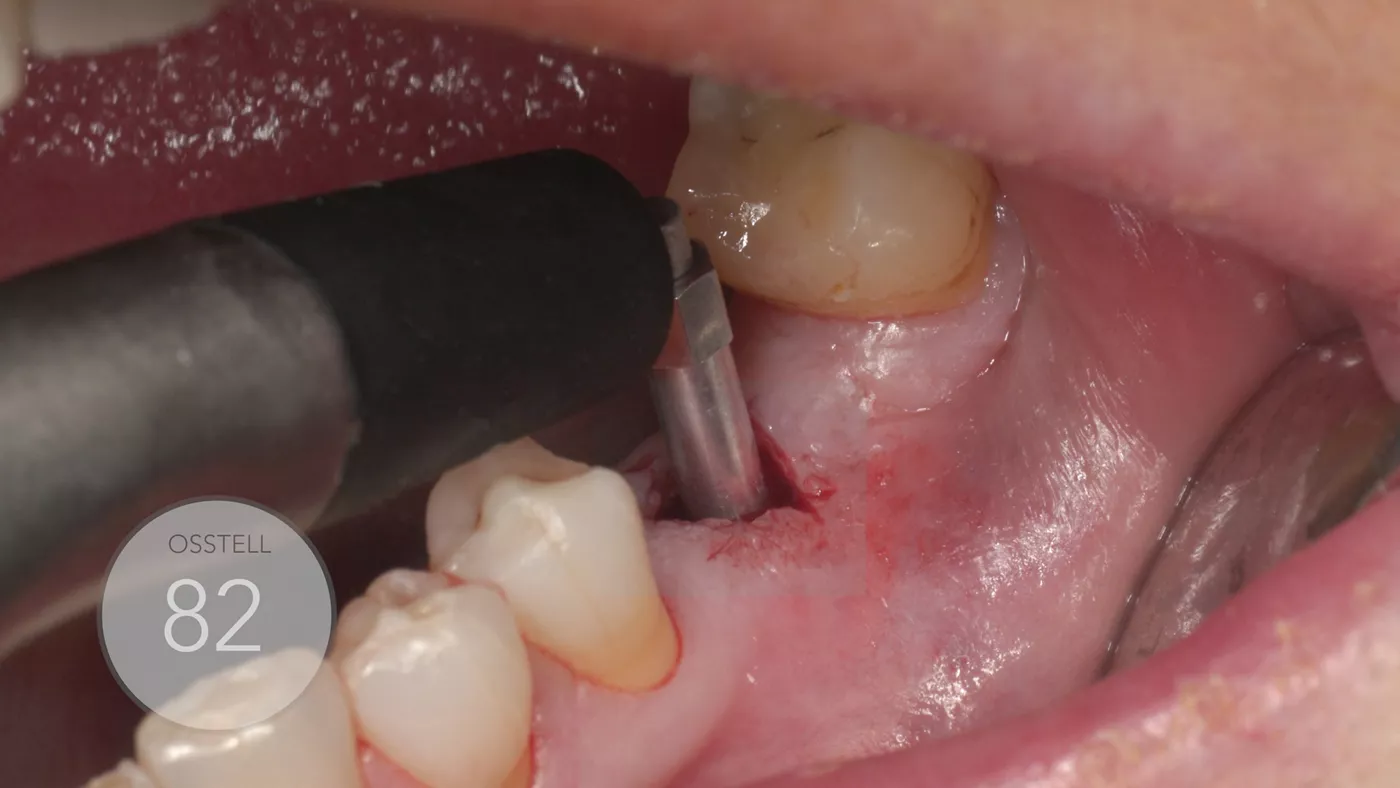

The ISQ level was determined with the Osstell unit. After connecting the Type 54 Smartpeg, a score of 82 was obtained (Fig. 12). The decision to employ an immediate loading protocol has to take account of the surgeon’s personal experience and skills, insertion torque, ISQ levels and medical and dental characteristics of the patient. In this case, all these parameters were evaluated as excellent, and the immediate loading protocol was selected.

fig. 12